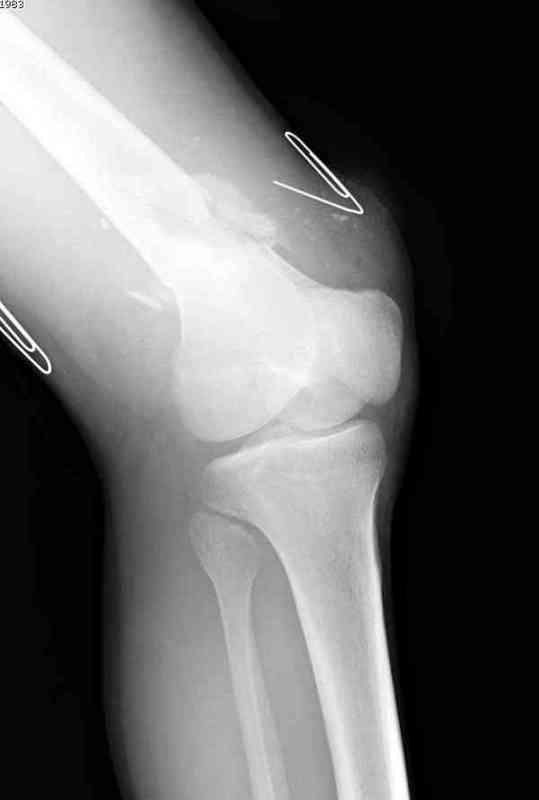

Пострадавшему 23, пистолетная огнестрельная не кроветочащая рана, меньше одного см диаметром, входное отверстие расположено латерально, и выход передне-медиально, и еще имеется второе пулевое ранение правой navicular bone с этой стороны.

Несмотря на сниженный до 0.9 BI-ankle-brachial-index (обязательное, недорогое исследование при подозрении на повреждение сосудов, рассчитанный по разнице давления в нижней и верхней конечности), последующее КТ ангиограмма не подтвердила повреждения артериальных сосудов.

Доступ был латеральный, при вскрытии с задней

поверхности бедра обнаружили кровотечение. Поднятием давления на заранее установленном турникете на конечности проконтролировали кровотечение.

В данном случае мы не ставили осуществление гемостаза приоритетным, после 30 минут больной оставлен вызванному сосудистому хирургу со стабильной фиксацией бедра. Несмотря на выбранный передне-медиальный доступ, хирург произвел восстановление сосудистого повреждения.

При близости сосудов к многооскольчатому повреждению костей, сперва необходимо удостовериться в наличии повреждения сосудов без применения турникета.